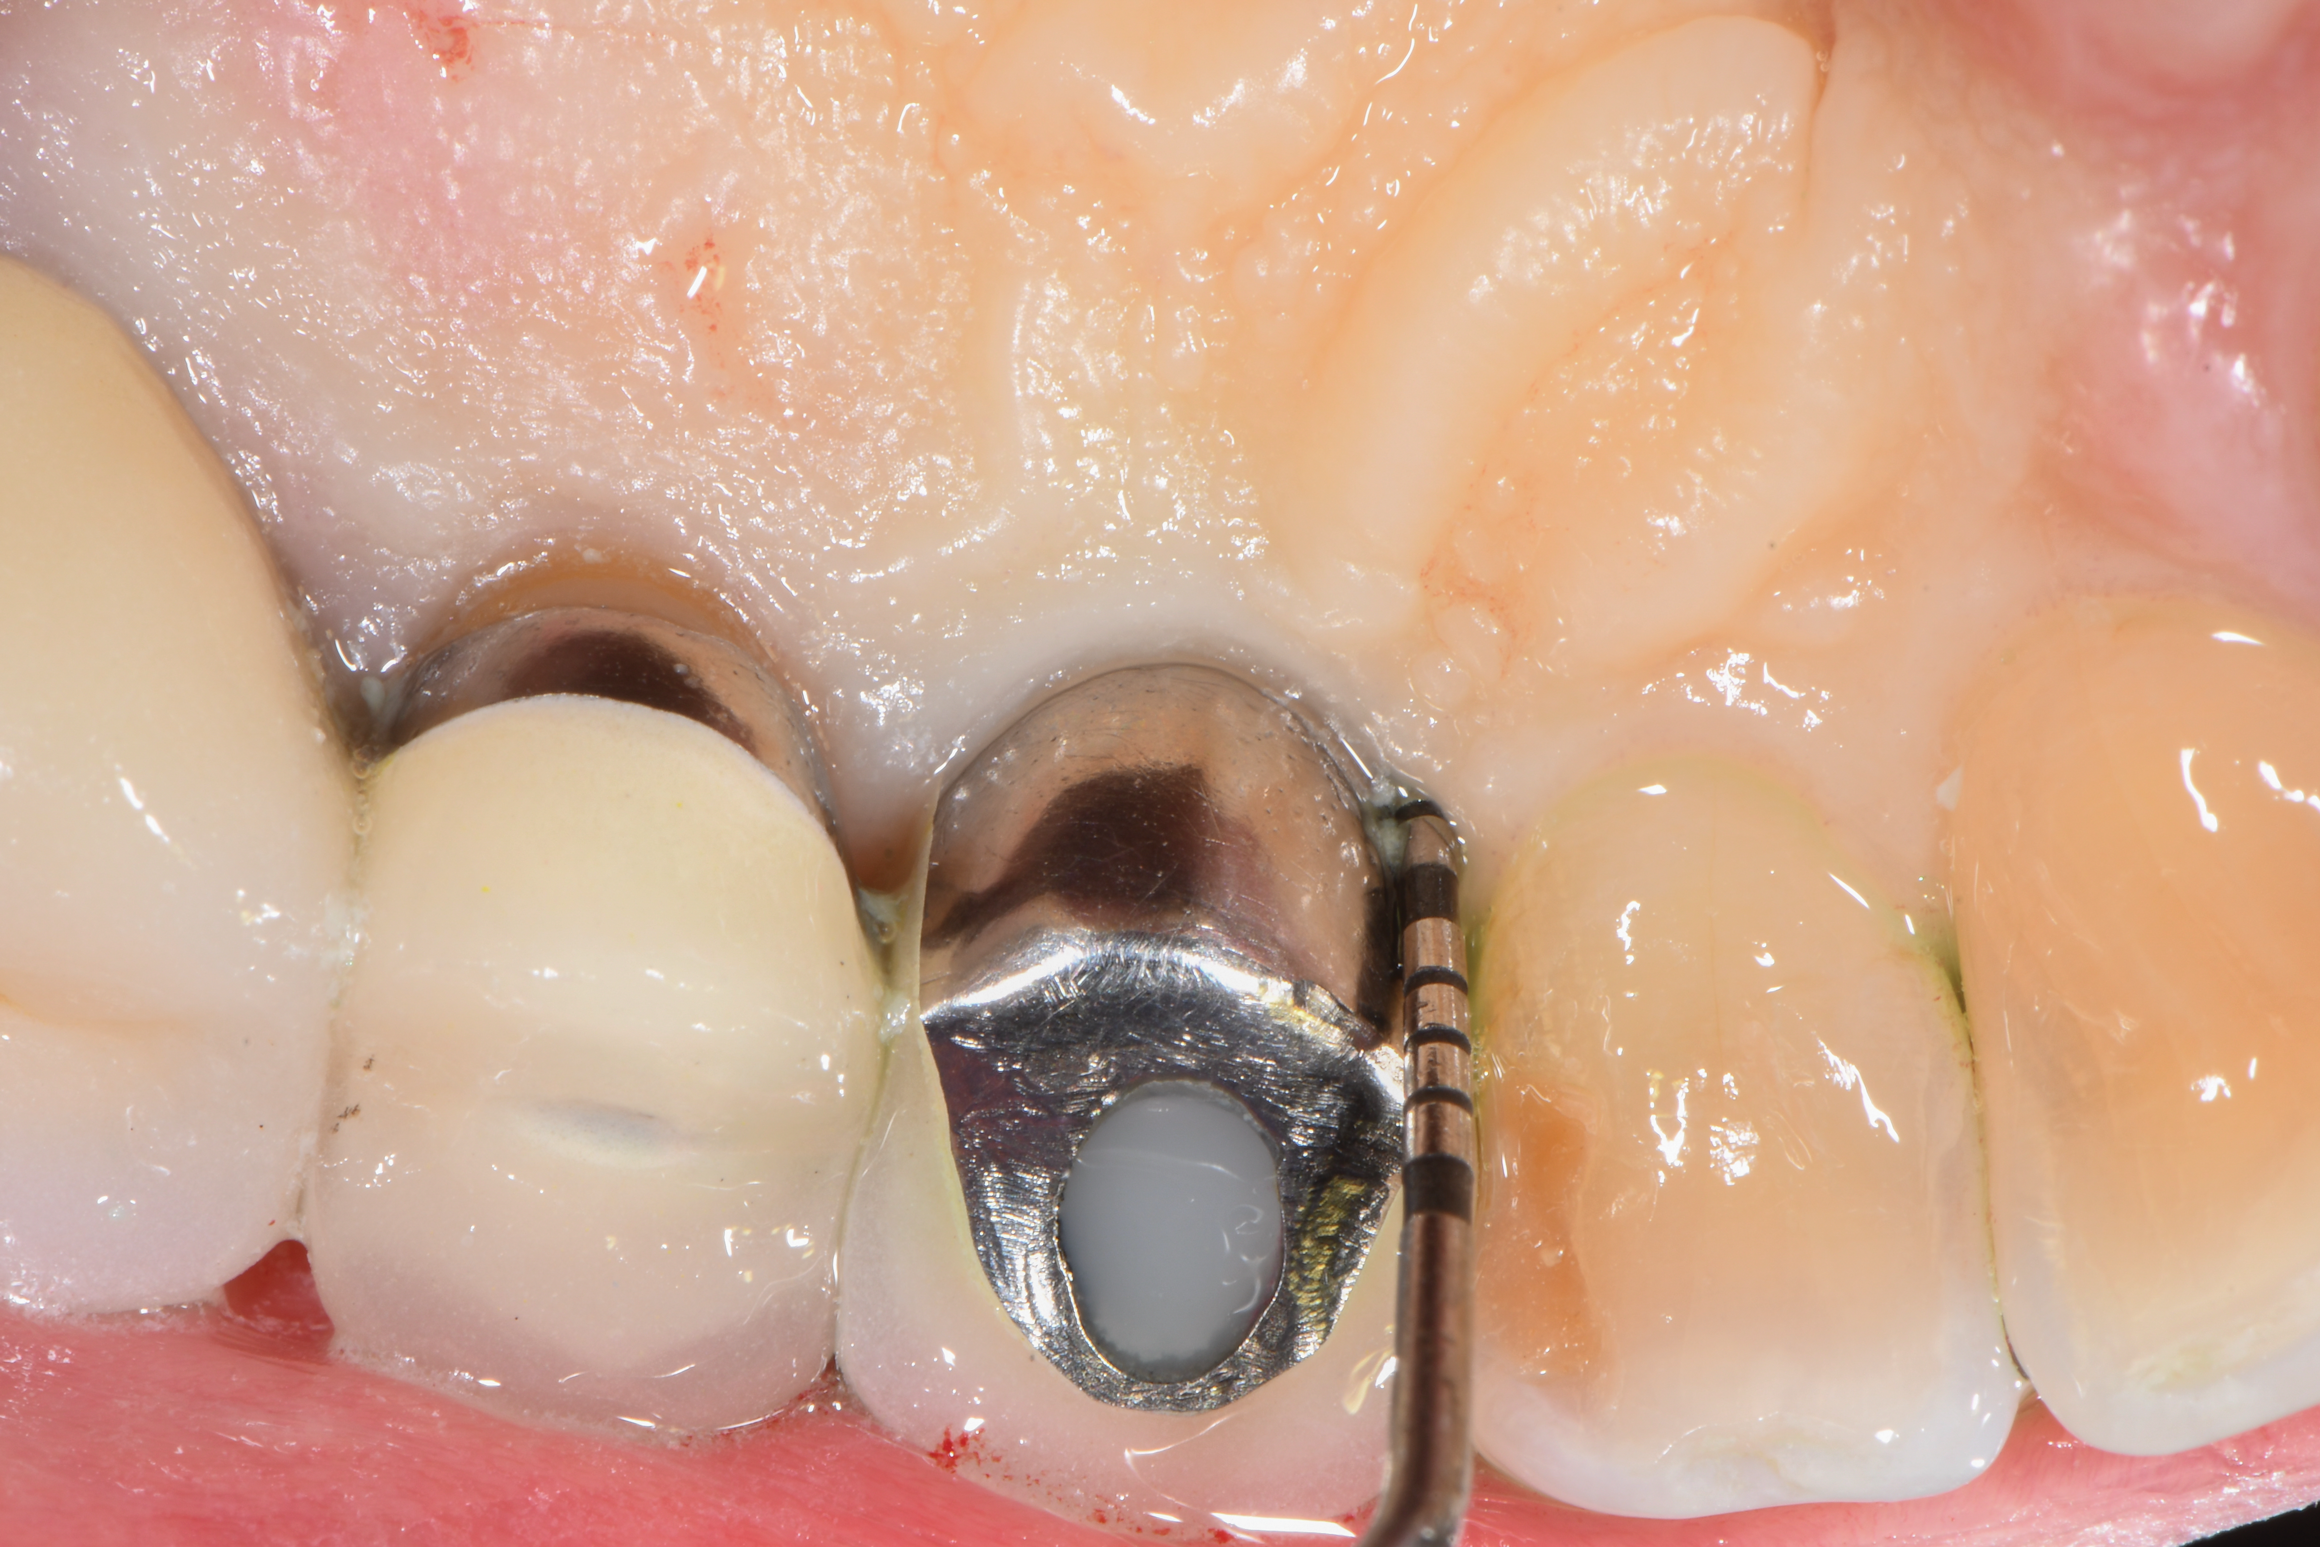

After local anesthesia was administered, full-thickness flaps were elevated from the buccal and lingual aspects of tooth No. 27 to the distobuccal and lingual aspects of tooth No. 31. Removal of granulomatous tissue from the implant site allowed visualization of a combination lesion with two walls at the distal and two to three walls at the mesial with a circumferential configuration on the lingual (Figure 12). The surface was initially treated with a 50% solution of citric acid for 30 seconds, which was burnished on with cotton pellets followed by thorough rinsing with sterile saline. This was followed by implantoplasty using 12-fluted followed by 30-fluted surgical-length finishing burs that provided access to the base of the defect. Because the crown was cemented, which obviated access, a matte-like surface could not be achieved; thus, the goal was to reduce the threads and remove the outer affected surface to expose fresh titanium (Figure 13). At this stage, the implant was wiped again with citric acid and rinsed with sterile saline.

Fig 12. The lesion was visualized upon flap reflection. A three- to two-wall lesion on the mesial wrapped to the lingual, while the distal had a two-wall lesion that also extended to the lingual as a moat.

Figure 12

Fig 13. Implantoplasty was completed. Some bleeding at the distal obscured one thread that was impossible to plasty. The surface was subsequently wiped with citric acid prior to grafting.